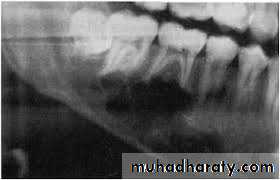

- Appear either as unilocular or multilocular configuration,

Cortical expansion, occasionally with perforation

- Teeth are typically displaced rather than eroded.